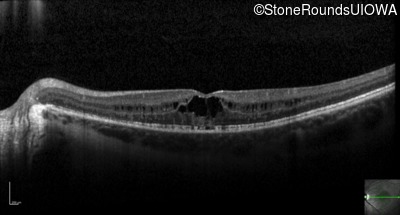

Optical Coherence Tomography - Right - 20/40 +1

Exemplar / OCT Stack